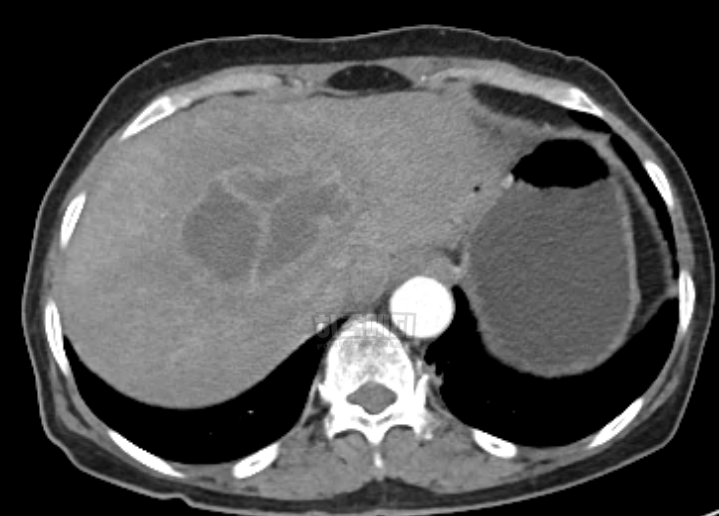

7) 간 초음파, CT, MRI

간 초음파, CT, MRI는 간의 구조적 문제나 질환을 더욱 정확히 확인할 수 있는 영상 검사입니다. 간의 크기, 형태, 결절 등을 확인하고, 간 질환이나 암의 유무를 확인하는 데 도움이 됩니다. 간 초음파는 비침습적이고 빠르게 진행할 수 있는 검사로, 주로 간염, 지방간, 간경변 등을 확인하는 데 사용됩니다.